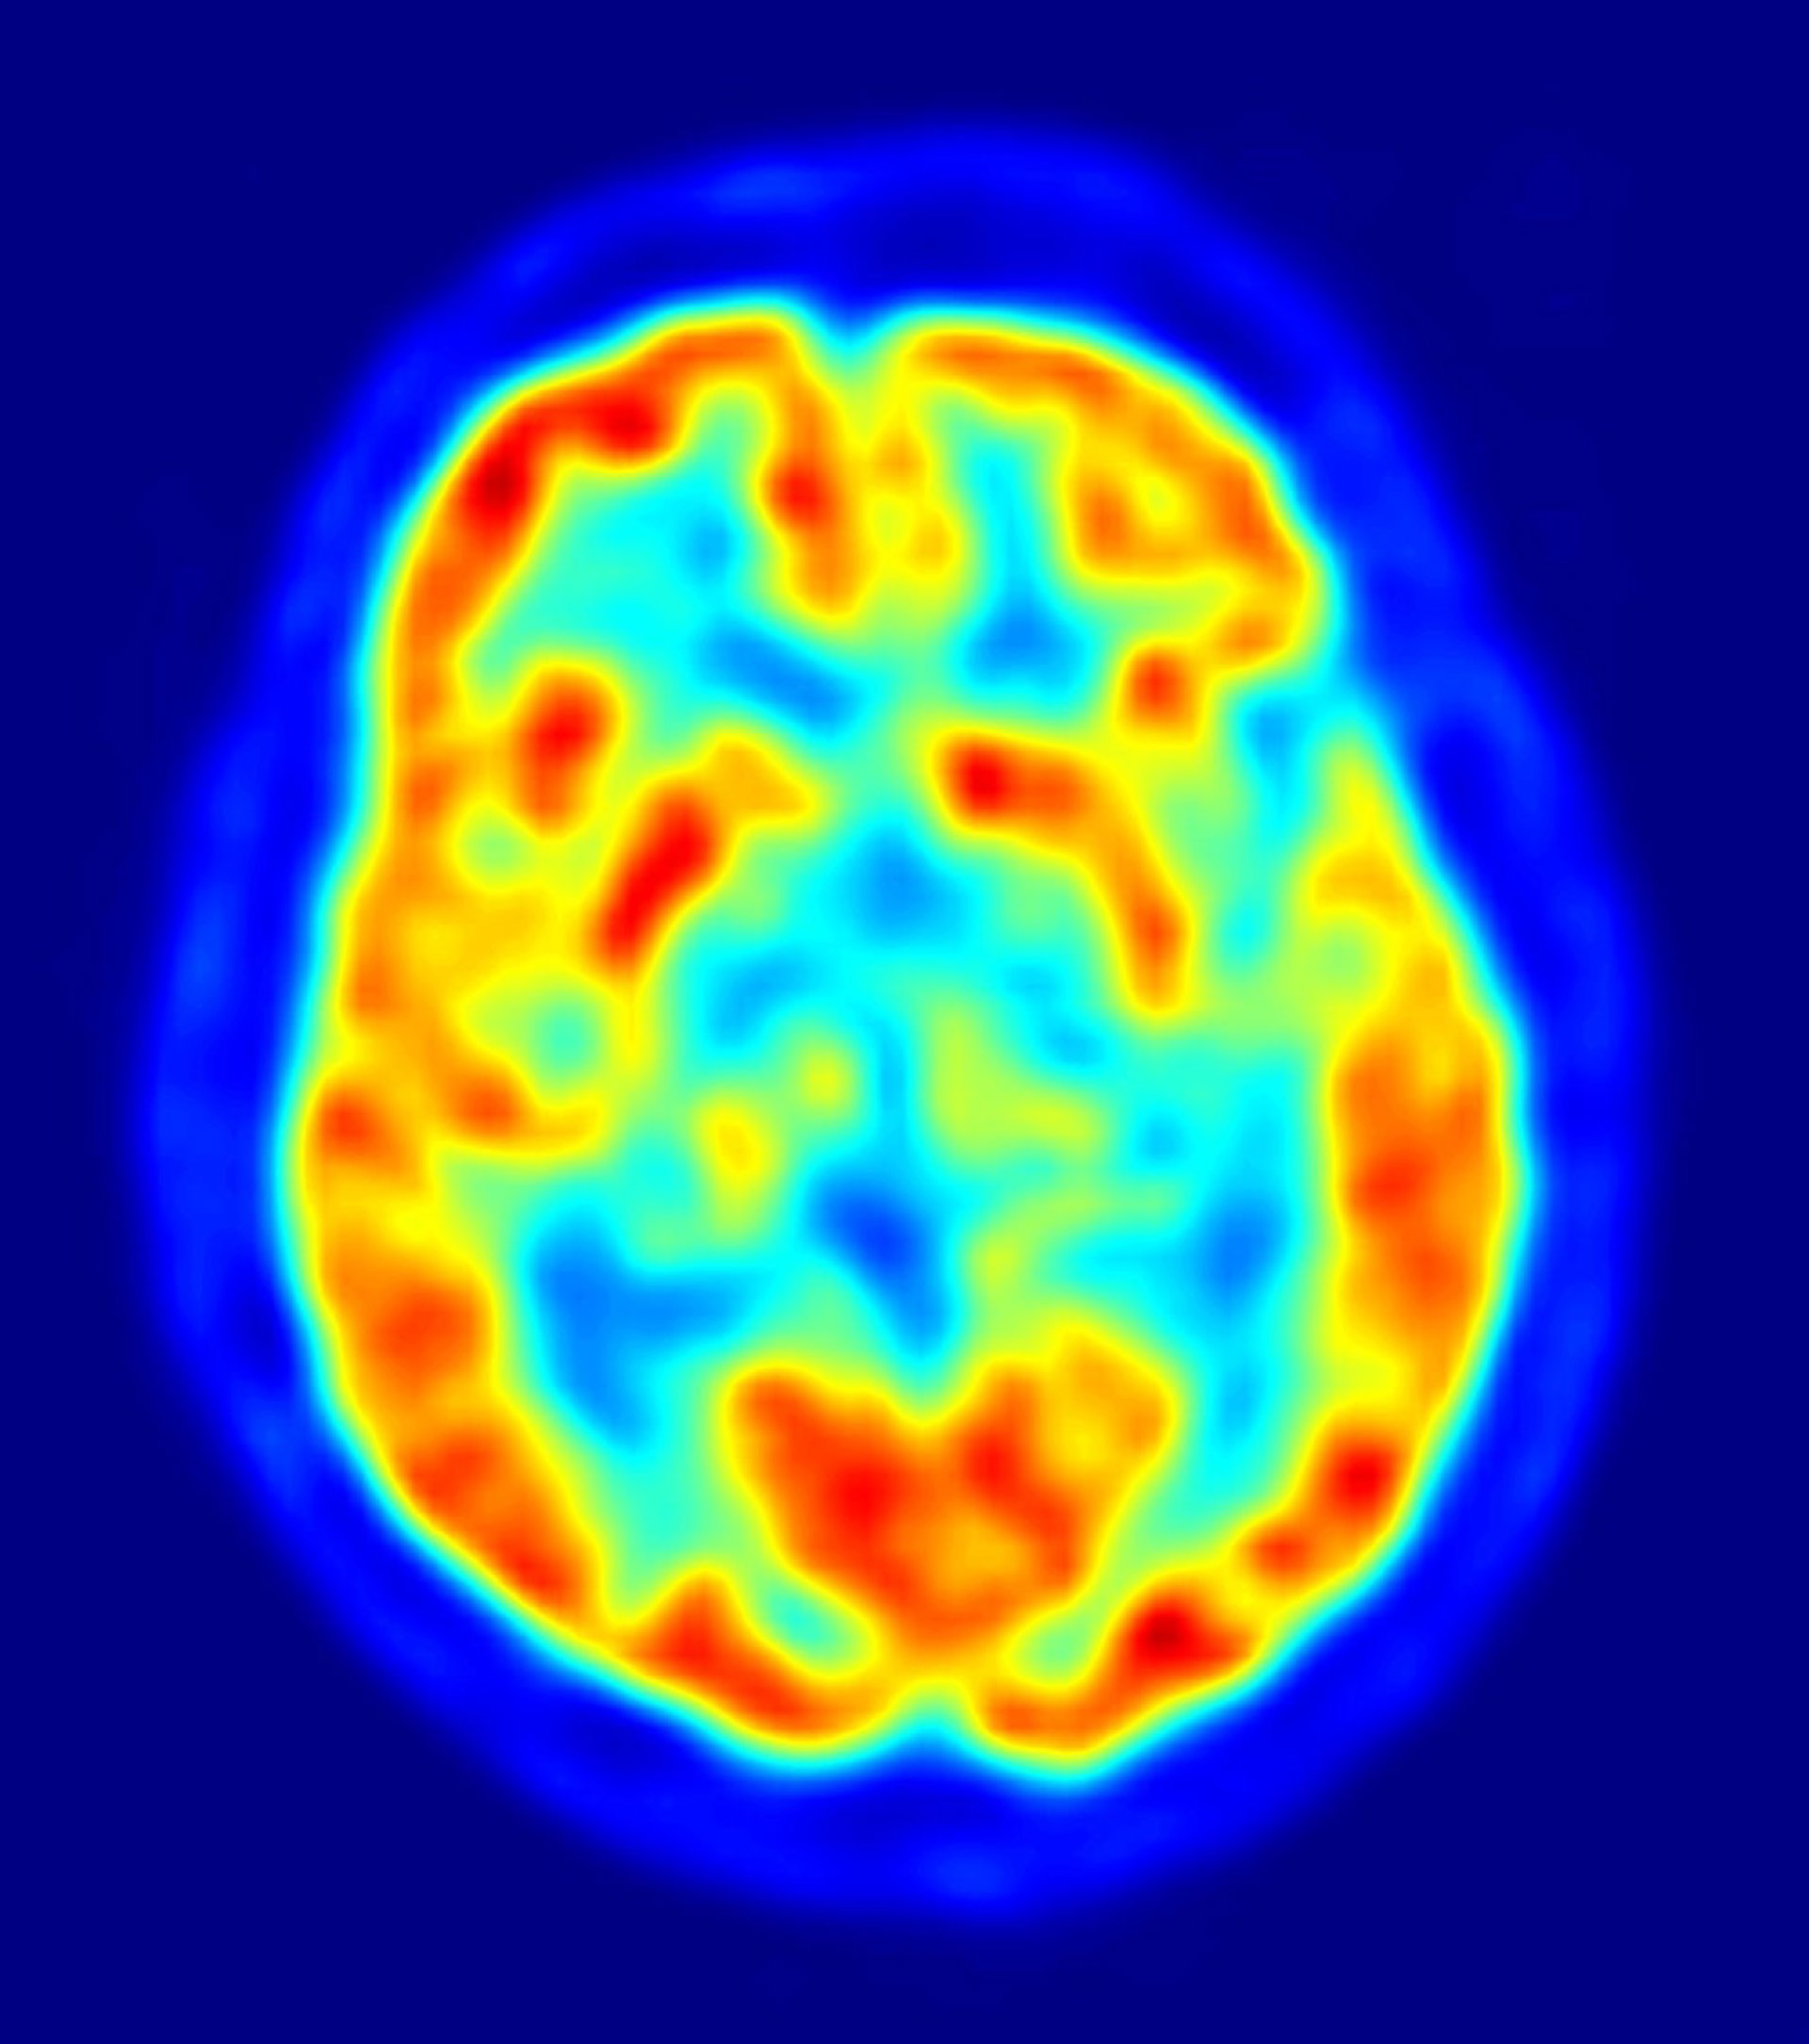

Investigadores del Grupo de Fisiopatología de la Enfermedad del Alzheimer del área de Neurociencias del Instituto de Biomedicina de Sevilla (IBIS) están analizando cómo retrasar las consecuencias del Alzheimer mediante el estudio de las células microgliales, que forman parte del sistema inmune del cerebro y que se activan de forma "excesiva" con la aparición de la enfermedad.

El objetivo es esclarecer si la respuesta inmune puede estar implicada en la degeneración de las células neuronales y con ello diseñar una posible terapia para retrasar los efectos de la patología. En este sentido, los expertos emplean técnicas de bioquímica, biología molecular y biología celular, es decir, cultivos de tejidos, animales transgénicos, muestras humanas y preparando nuevos animales para ver cómo se comporta el sistema inmune cerebral.